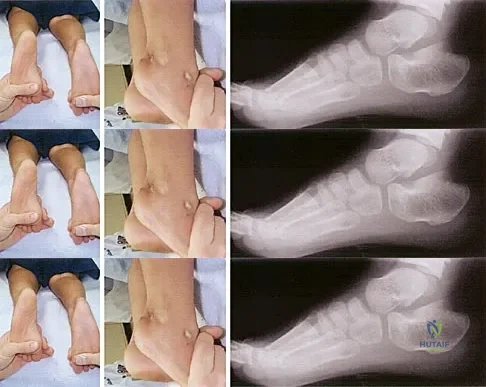

Examination of a 12-year-old girl with a painful flatfoot deformity reveals tenderness in the region of the sinus tarsi and no appreciable subtalar motion. Radiographs are shown in Figures 48a through 48c. Two attempts to relieve her symptoms by cast immobilization fail to relieve the pain. Management should now consist of

Explanation

A 16-year-old boy has a symptomatic flatfoot deformity that is causing pain, skin breakdown, and shoe wear problems. Shoe modification and an orthosis have failed to provide relief. Examination reveals hindfoot valgus, talonavicular sag, and forefoot abduction that are all passively correctable. Treatment should consist of

Explanation